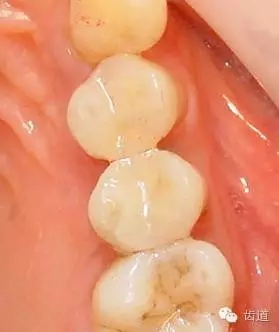

1、磨牙近中崩折舌面行嵌體牙體預(yù)備后

2、金屬鑄造嵌體

3、磨牙金屬鑄造嵌體粘固后